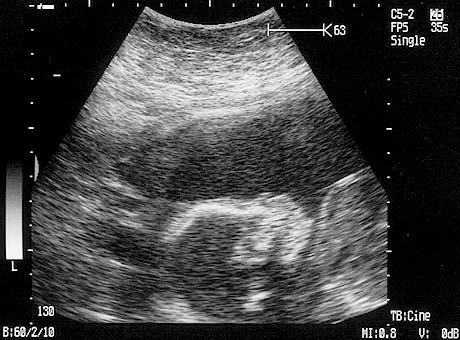

June 2006

Rockwell Baby